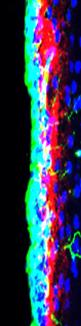

image: The blood clotting protein fibrinogen (red) is deposited in the stem cell niche and regulates the contribution of stem cells (green) to repair mechanisms in central nervous system diseases.

Schachtrup and his team show that, following damage to the cerebral cortex of mice, fibrinogen from the blood is enriched in the stem cell niche of the SVZ, which is located further inside the brain. Fibrinogen is a blood coagulation factor and a precursor of the protein fibrin, which coats and stabilizes the blood platelets that gather at the site of a vascular injury. Fibrinogen inhibits the neuronal differentiation of NSPCs, the researchers discovered. At the same time, the enriched fibrinogen leads to increased astrogenesis, i.e. the formation of new astrocytes, as fibrinogen activates the so-called BMP receptor signaling pathway. By experimentally reducing fibrinogen, for example by adding the snake venom Ancrod, the astrocyte formation from NSPCs was blocked, which is why only reduced scars developed.